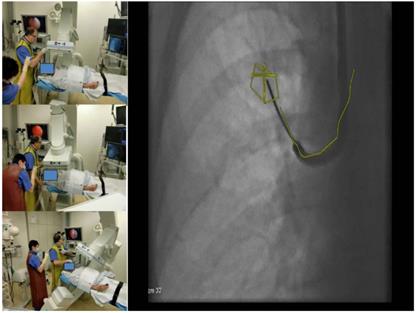

9.  Figure 7

3edge angulations with 3 different views at least 30 degrees different to each other and with one oblique view.

8. Navigation control is achieved by the so called 3-edges-angulation during this period of perfect alignment. From a posterior-anterior position of the DynaCT-head one has to angulate thirty degrees lateral, then follow with another angulation of thirty degrees caudal or cranial and finally angulate thirty degrees medial. (Figure 7.) The examiner has to compare these 3 views of the used endobronchial probe under fluoroscopy with the virtual anatomy overlaid in the fluoroscopy image: If we observe that the probe in all views stays in the virtual path segmentation or the target volume we can conclude that it has reached the desired anatomical position endothoracically. The number of 3-edges angulations needed depends on the complexity of the path and the endoluminal entry into the target. During the examination time when no navigational decision is needed we apply normofrequent jet-ventilation (e.g. RF 80/min; I: E 1:1, 5; SIWP in regards to blood gases).